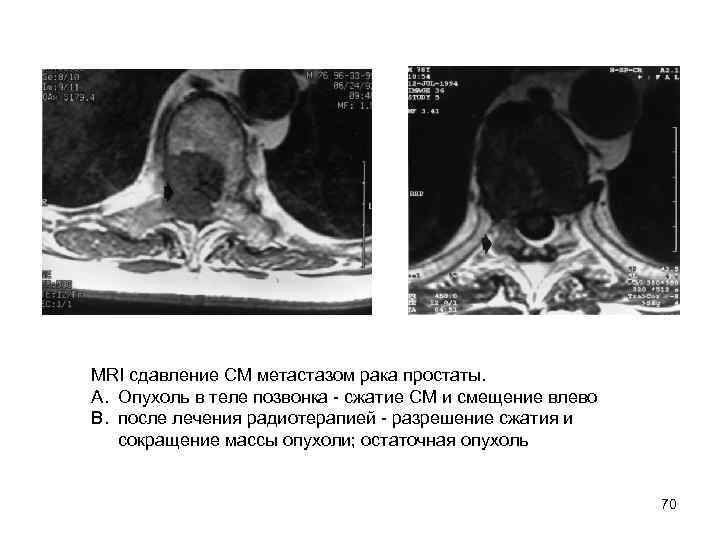

MRI сдавление СМ метастазом рака простаты. A. Опухоль в теле позвонка сжатие СМ и смещение влево B. после лечения радиотерапией разрешение сжатия и сокращение массы опухоли; остаточная опухоль 70